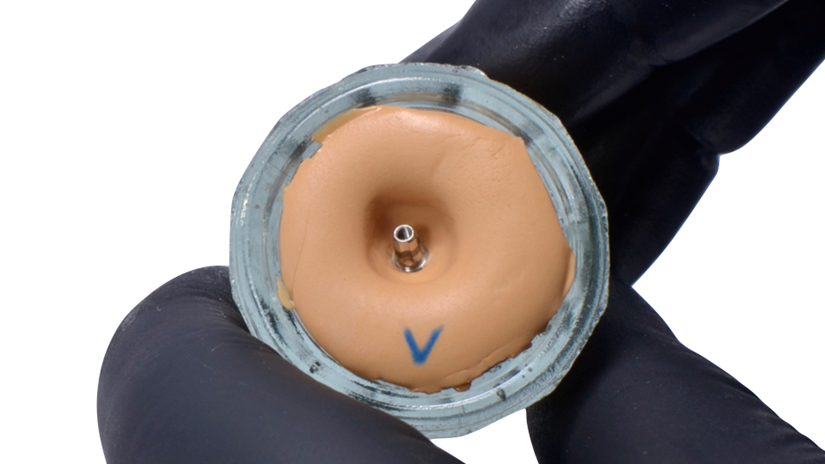

A paciente apresentava queixas estéticas e funcionais. Após avaliação clínica e radiográfica, optou-se pela substituição do pilar reto por um pilar Ideale angulado de 17 graus e 3,3 mm de diâmetro. Esse componente mais estreito e angulado permitiu corrigir o eixo emergente da futura coroa, viabilizando o planejamento de uma prótese parafusada na região estética.